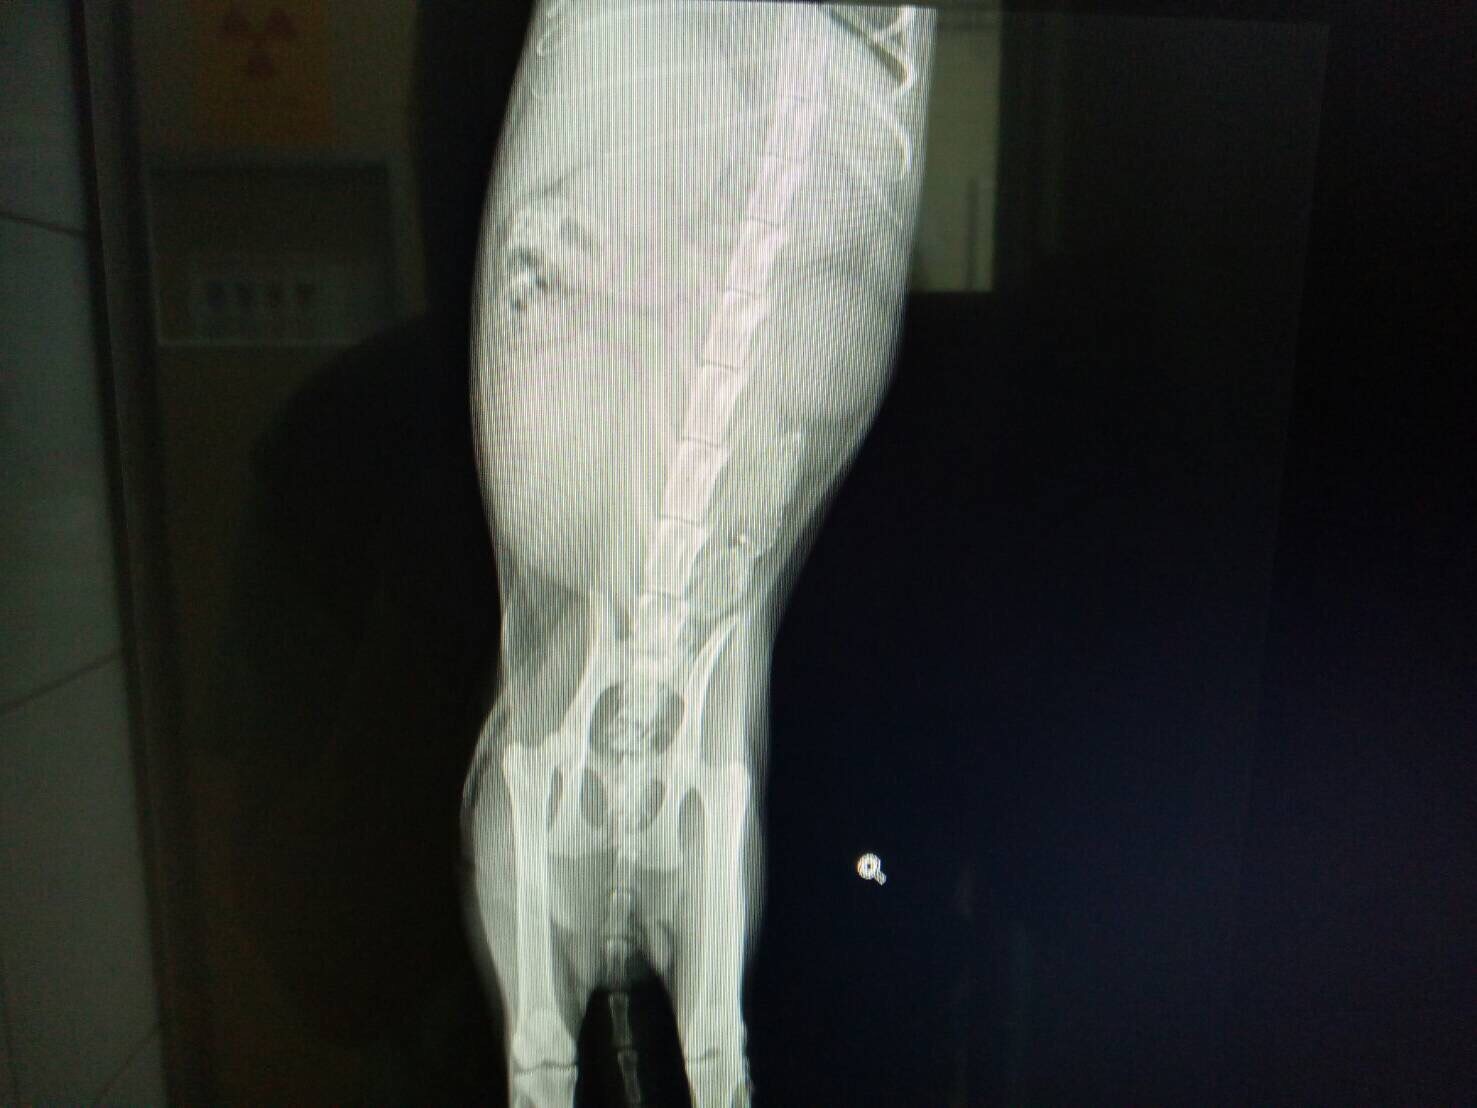

主題: 四肢多處蜂窩性組織炎引發敗血症大貓 申請者姓名: 歐陽妃 花色: 申請日期: 2017-02-20 11:59:47 申請者部落格: 申請者臉書網址: https://m.facebook.com/profile.php?id=100002589566051 所在縣市/合作醫院: 高雄市/泰安動物醫院 治療費用: 24000元 需求人數: 26人 已結案 (2022-05-13 15:16:09) 報名人員: Kitty Chen(已付款)、黃家姊妹(已付款)、Kitty Chen(已付款)、Bobbie Chen(已付款)、May(已付款)、Vicky Tung(已付款)、張嘉琪(已付款)、蘇小今,廖哈尼(已付款)、吳點點(已付款)、梁仕宏(已付款)、Ming Yi(已付款)、琳恩(已付款)、youngshiang(已付款)、Ikkuka(已付款)、二虎(已付款)、Tomato(已付款)、Iris Hsu(已付款)、捲捲米花 x2(已付款)、Min Yi Inc.(已付款)、Midori(已付款)、桔比(已付款)、Amber x2(已付款)、曾瑪格(已付款)、佩佩灰貓(已付款)、 候補人員: 動物病情說明: 大虎是路倒在路上的浪浪,病懨懨的躺著一動也不動,二話不說立刻回家拿籠子衝去救援,他的屁股那裏有一個很大的洞已經潰爛嚴重,四肢沒有一隻腳是完好無傷的,尤其後肢關節處嚴重潰爛見骨,可能因為身體太虛弱需要求助才路倒在路上,立刻送最近的合作醫院。到院時醫生立即檢查全身傷口潰爛的地方抽血做完血檢後發現白血球指數高出正常值非常多,剃毛要做點滴輸液治療時也發現四隻瘀青腫脹,研判因為多處潰爛嚴重導致敗血症,體溫也因傷口潰爛發燒,先做清創手術治療! 動物近況說明: 就醫時外觀傷口化膿,清創手術發現臀部內部大面積潰爛,當時狀況非常糟糕,血檢指數白血球飆高引發敗血症,靠著打抗生素和他自身的求生意志,經過兩個多月的持續清創和照護終於存活下來,似乎也很感恩似的,一點都沒有浪貓的警戒,反而是一直找人撒嬌討摸,原本預計紮回原放,考量到他的個性極為親人,目前安置在醫院內等待認養人∼